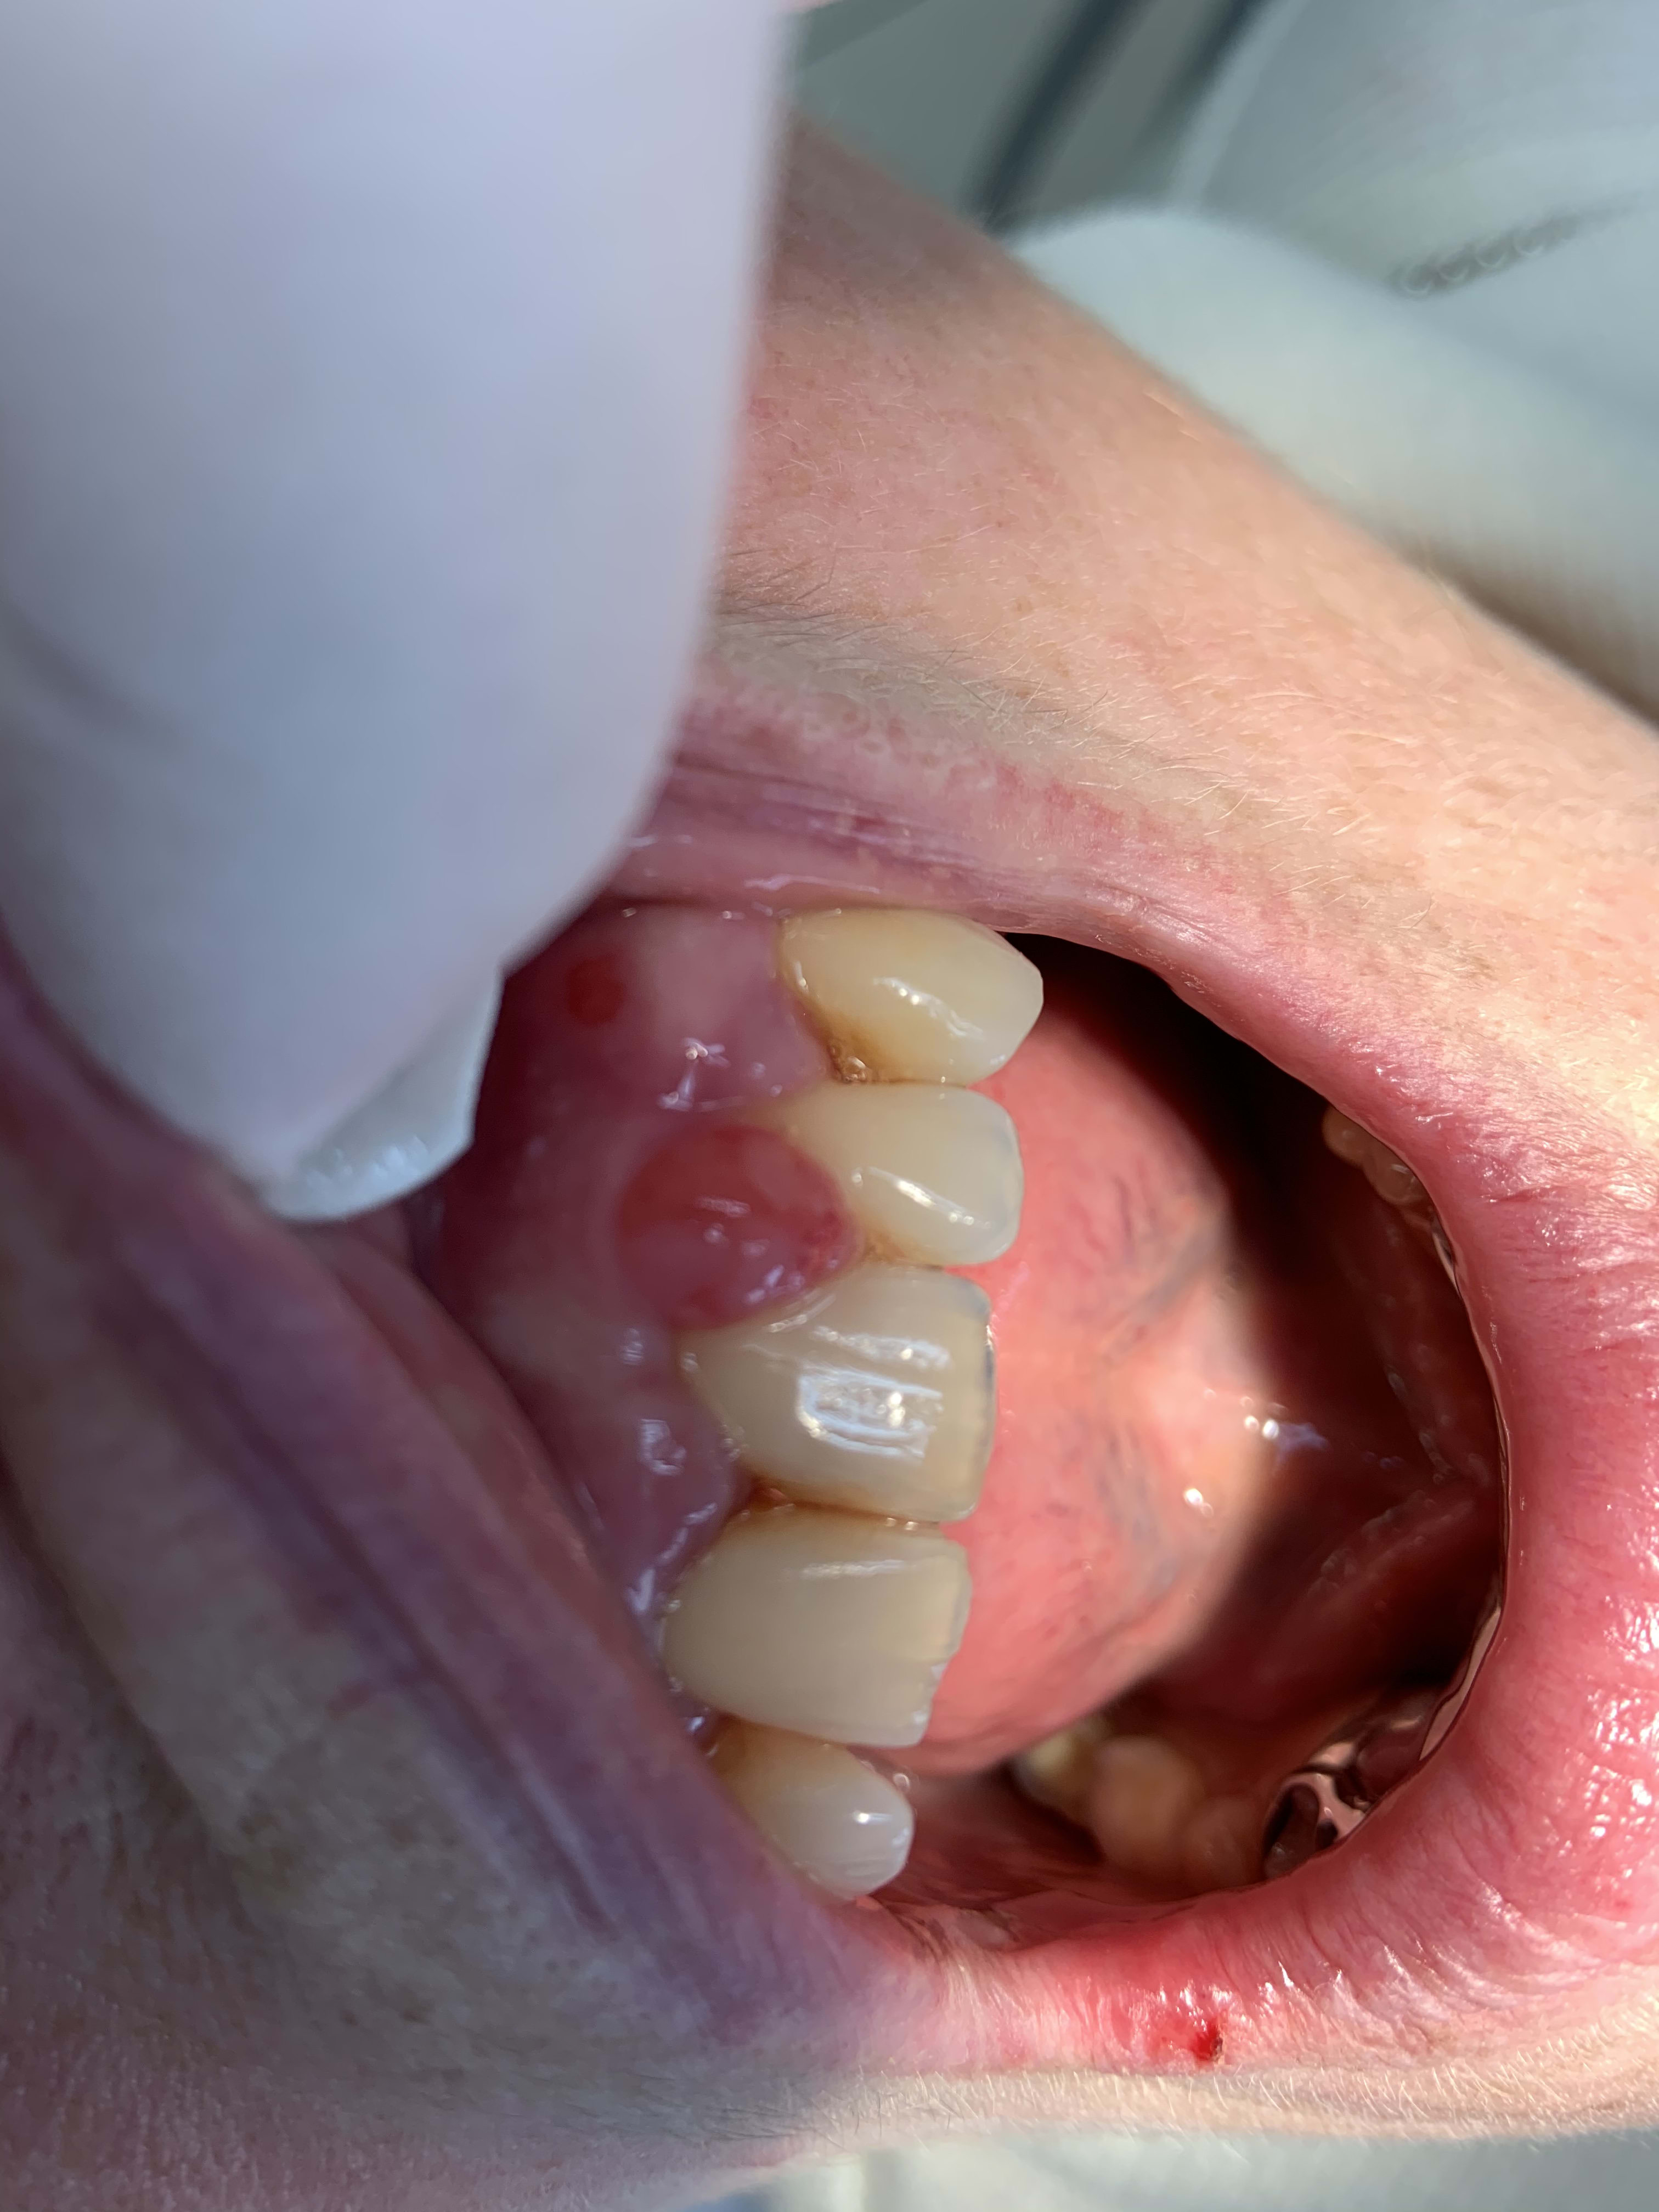

Bonjour je vous envoie la photo d’une excroissance gingivale au niveau d’une 22 chez une patiente sous Coumadine (anti vit K). Quelle serait votre procédure ? Je demande un INR si c’est entre deux et trois je peux tout simplement le supprimer ?

GUN je ne sais pas, mais en tout cas çà n'a pas l'air très propre tout çà.

Tu as pensé à nettoyer/cureter/détartrer/surfacer? Vu la tête du machin, il doit y avoir des trucs (plaque/tartre/bactéries) derrière/dessous.

Faire une exérèse sans résoudre la cause, c'est pas top.

Ok bien sûr pour le détartrage ,ce qui m’inquiétait c’est l’hémorragie,d’autant que je n’ai pas de bistouri électrique.